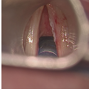

Soprattutto se persistenti, è necessario eseguire una visita e una laringoscopia per valutare attentamente sia la morfologia che la motilità della laringe.

Anche nell’anziano possono verificarsi fenomeni simili (presbifonia), legati ad un deficit tenso-adduttorio delle corde vocali. Uno studio del distretto faringolaringeo con una laringoscopia a fibre ottiche o fibrolaringoscopia rappresenta il primo step per poter identificare il disturbo e procedere ad un trattamento adeguato.

Nell’ambito delle patologie neoplastiche occorre distinguere le lesioni precancerose e i tumori maligni veri e propri. Nel primo caso si tratta di lesioni delle corde vocali caratterizzate da atipie istologiche ad alto rischio di trasformazione maligna, come la leucoplachia, che si identifica come una lesione di aspetto biancastro della corda vocale.

I tumori della regione glottica, invece, sono tra le neoplasie più frequenti del testa-collo. La loro incidenza è significativamente più alta negli uomini e il fattore predispondente principale è il fumo di sigaretta. Anche alcool, esposizioni a polveri di amianto e radiazioni ionizzanti sono ulteriori fattori di rischio per questo tipo di patologie. Il sintomo più frequente è un abbassamento di voce persistente, al quale possono associarsi anche disturbi deglutitori (disfagia) e, nei casi più severi, difficoltà alla respirazione (dispnea). Una diagnosi precoce di tali malattie è fondamentale in quanto, se individuate in uno stadio iniziale, il tasso di sopravvivenza a 5 anni è superiore all’80-90%. Il trattamento può essere chirurgico (cordectomia laser) o radioterapico.

tumore corda vocale